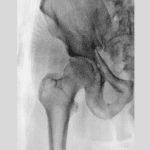

Hip Arthritis

The Hips are one of the most common places in the body which can be affected by arthritis.

As many different types of arthritis can impact the hip, the most important step in the treatment journey is getting an accurate diagnosis. Seeing your GP is a great place to start. In many cases a GP can diagnose your arthritis. However, if they are unsure or would like a second opinion they may choose to refer to you a specialist such as a rheumatologist or orthopaedic specialist.